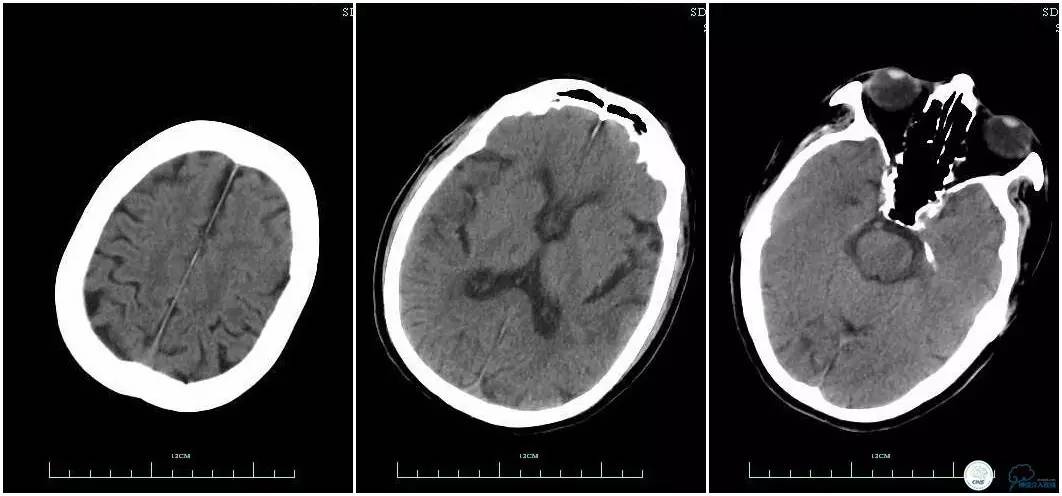

辅助检查:血常规、生化、凝血功能未见明显异常,心电图:窦性心律,ST-T改变;头颅CT平扫:未见明显出血。头颅MRI:未见新鲜梗塞灶;头颅MRA:双侧大脑前动脉远端缺如。

术前头颅CT平扫。

术前头颅MRI。

术前头颅MRA。